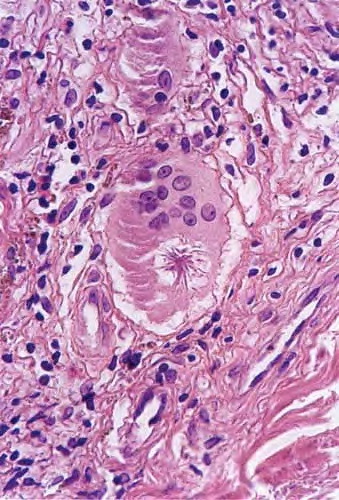

In typical cutaneous lesions of sarcoidosis, the well-demarcated islands of epithelioid cells contain few, if any, giant cells. Those that are present are usually of the Langhans type. A moderate number of giant cells can be found in old lesions. These giant cells may be large and irregular in shape. In a minority of cases, giant cells contain asteroid bodies or Schaumann bodies . Asteroid bodies , which are more common, are star-shaped eosinophilic structures that, when stained with phosphotungstic acid-hematoxylin, produce a center that is brown-red with radiating blue spikes . Schaumann bodies are round or oval, laminated, and calcified, especially at their periphery. They stain dark blue because of the presence of calcium. Neither of these two bodies is specific for sarcoidosis: They have been observed in a variety of other granulomas, including those of leprosy, tuberculosis, foreign-body reactions, and necrobiotic xanthogranuloma .

residual bodies of Iysosomes. Asteroid bodies consist of collagen showing the typical 64- to 70-nm periodicity. It seems likely that this collagen is trapped between epithelioid cells during the stage of giant-cell formation .